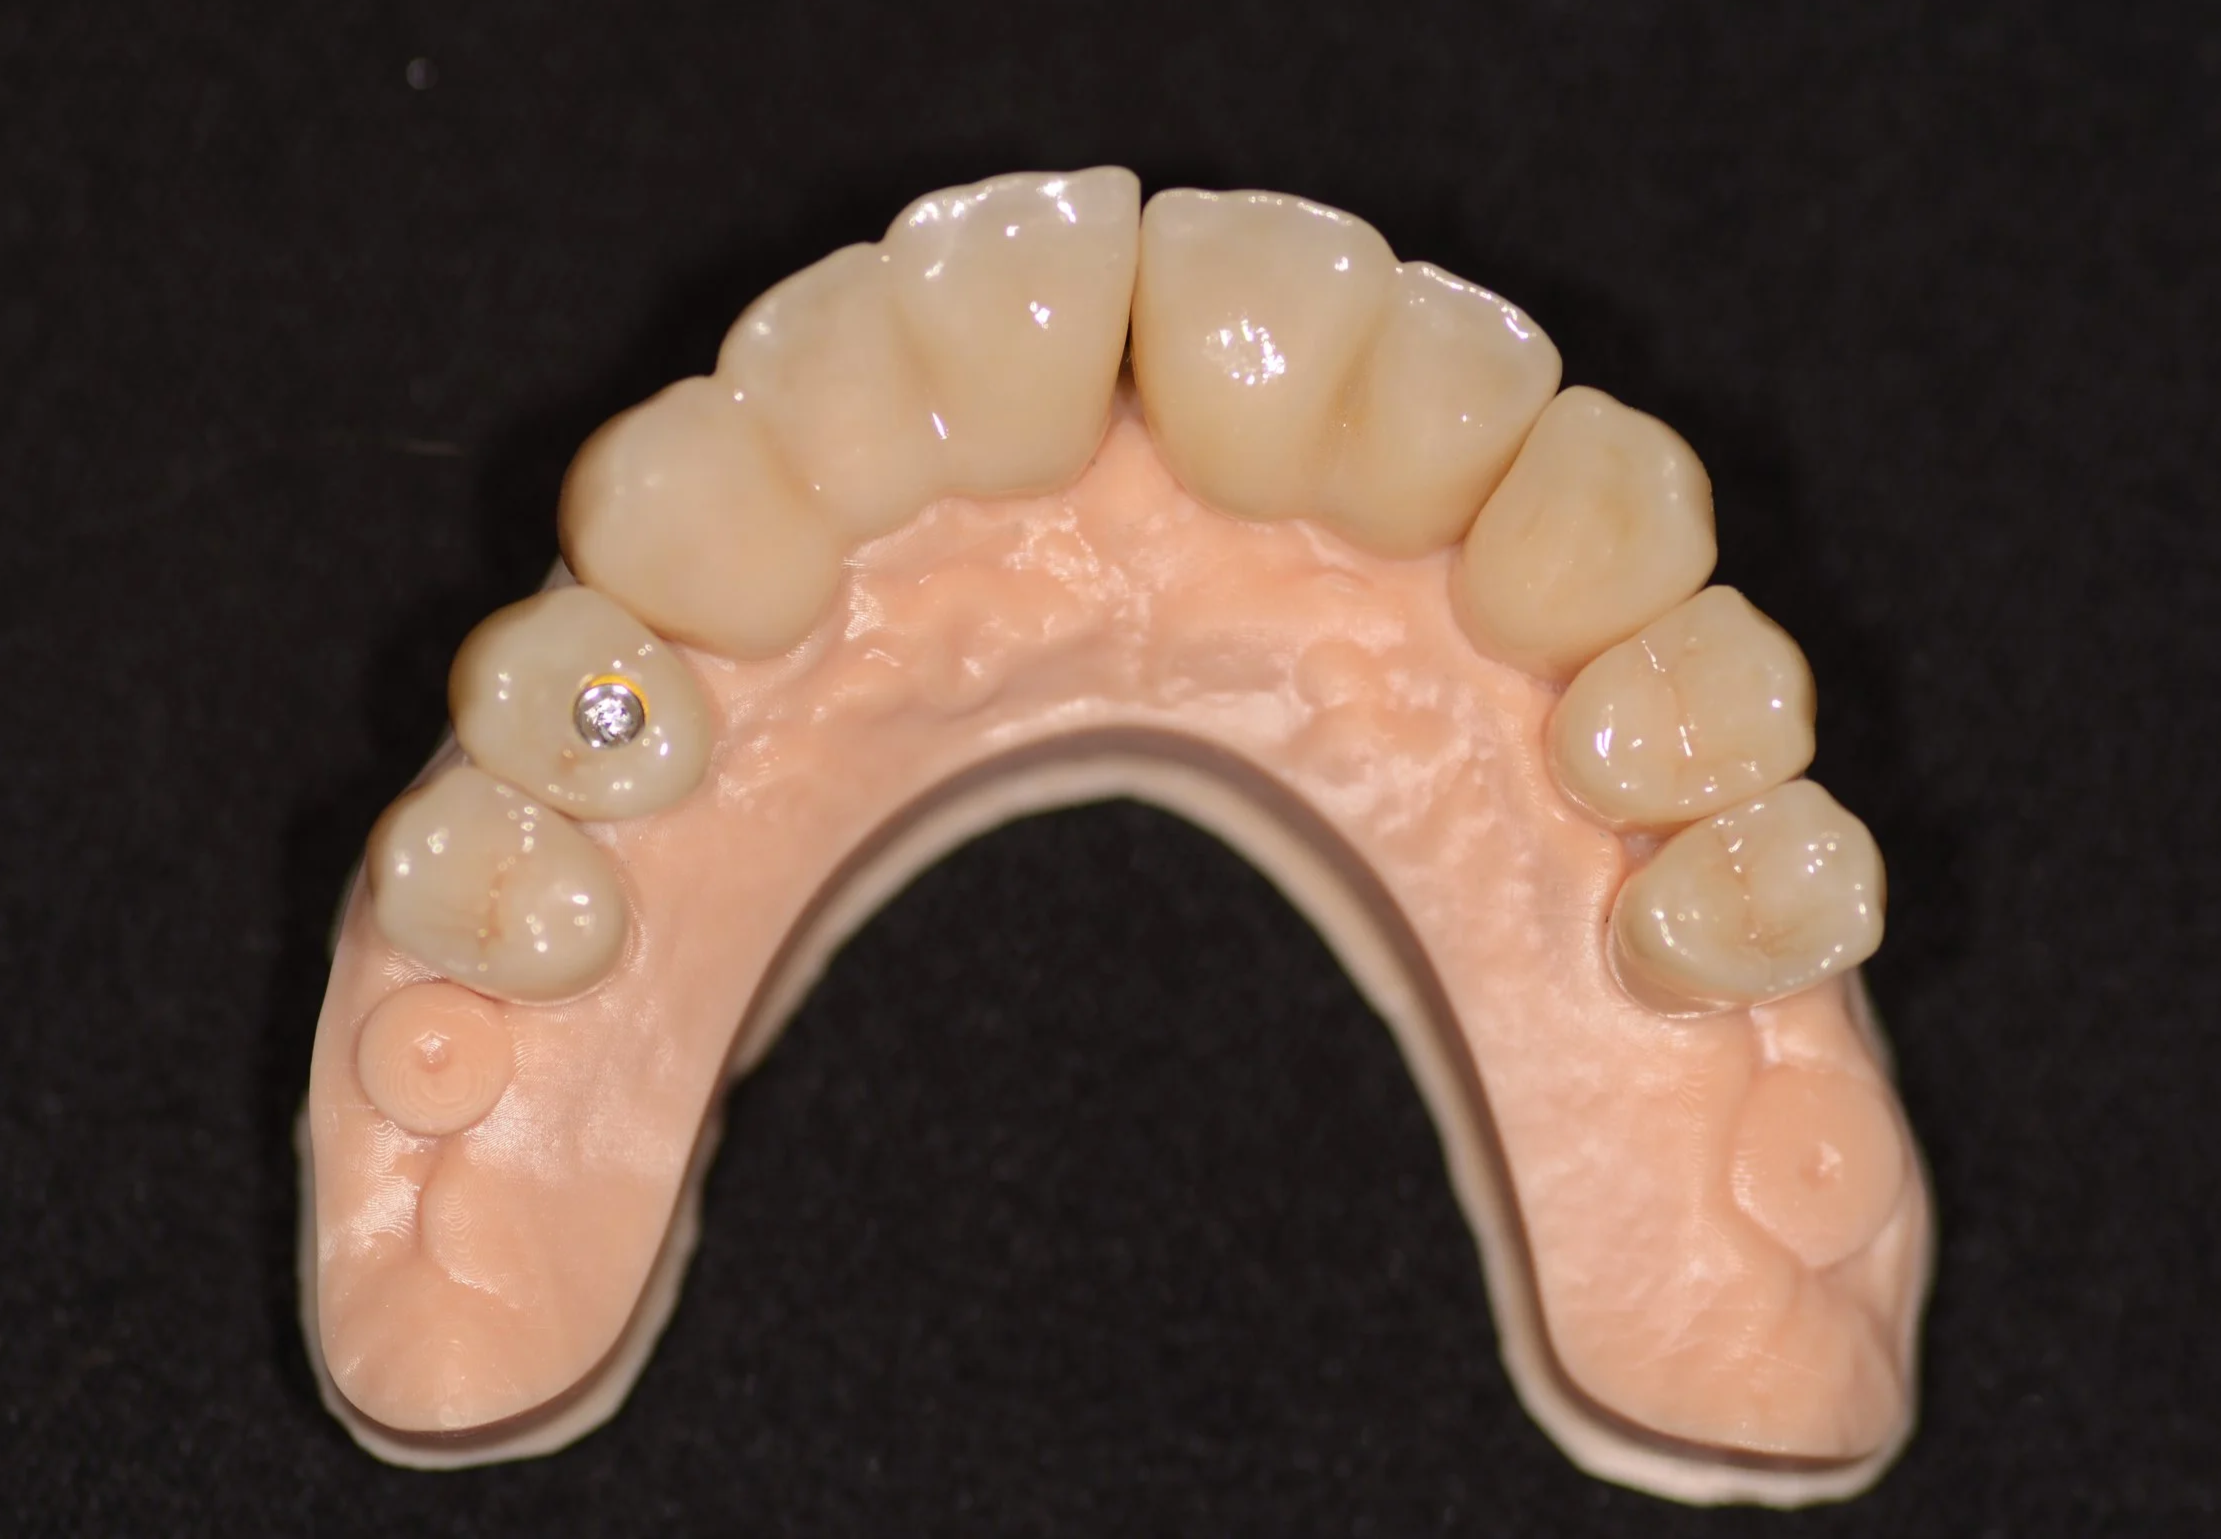

PLANIFICACIÓN: Se presentaron 3 planes de tratamientos, finalmente se decidió realizar reconstrucción fija superior e inferior.

RESULTADO FINAL: El paciente quedó conforme con el tratamiento, recuperó su salud, confort y estética.